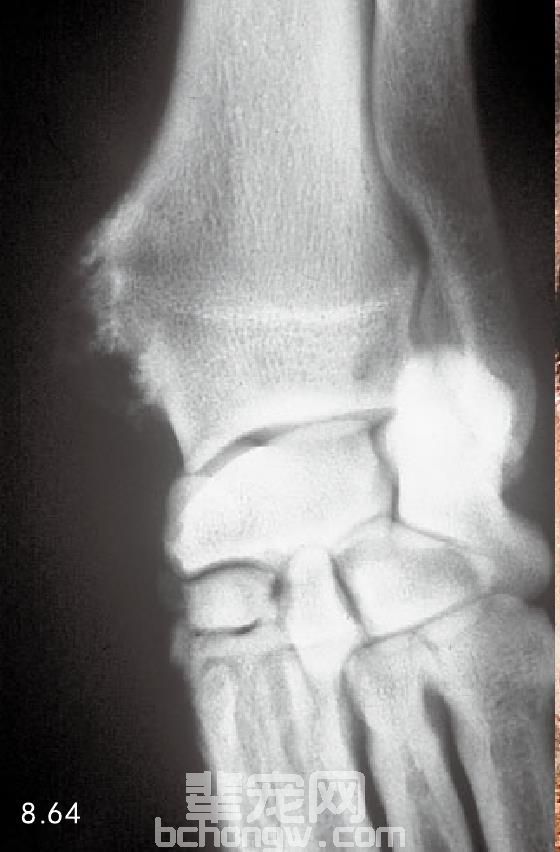

诊断 X线片显示有光滑的薄壳,发生在四肢的或者中轴骨骼骨皮质表面的骨骼团块(图8.64)。扩散的外 生骨疣会引起骨骼的变形。定期的X线检查有必要做,因为慢性的损伤可以转变为骨肿瘤。

图8.64 桡骨远端干骺端中间部位的软骨骨疣。